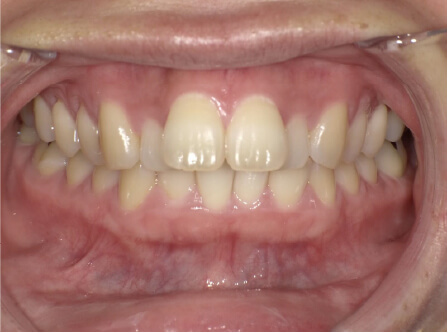

前歯前突の症例

8歳

男性

相談内容

前歯が気になる

カウンセリング・診断結果

前突・叢生 アレルギー有

治療内容・方法

全額アライナー矯正 上下拡大装置使用

術後の経過・現在の様子

上下リンガルアーチ使用

治療のリスク

痛み・歯根吸収・歯肉退縮・虫歯・後戻り

費用・治療期間

780,000円、1年8ヶ月